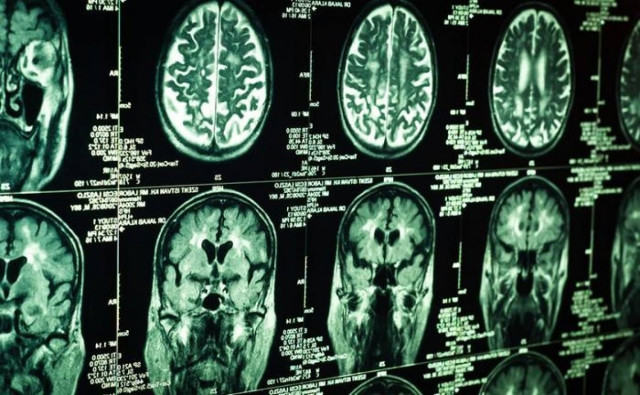

Μικρότερο εγκέφαλο, αλλά και προβλήματα όπως κατάθλιψη και άγχος, φαίνεται να έχουν τα παιδιά των οποίων οι μητέρες κάπνιζαν, κατά τη διάρκεια της εγκυμοσύνης, σύμφωνα με μία πρόσφατη έρευνα, που πραγματοποιήθηκε στο Ιατρικό Κέντρο «Erasmus», στο Ρότερνταμ της Ολλανδίας και δημοσιεύεται στο επιστημονικό περιοδικό «Neuropsychopharmacology».